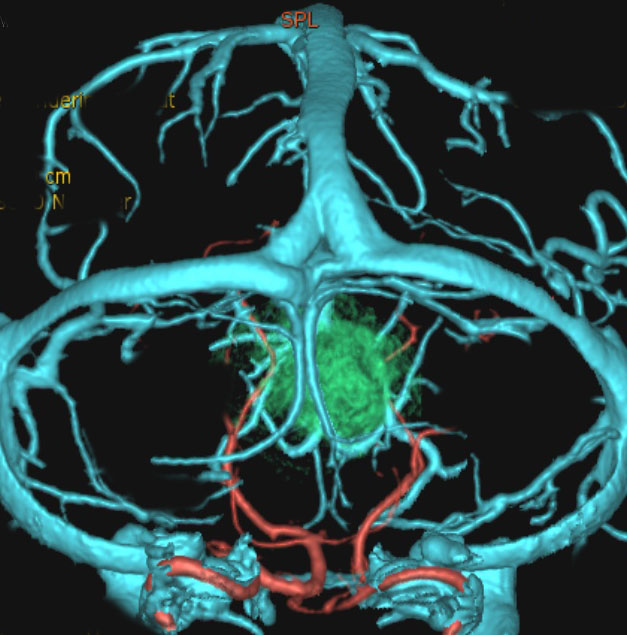

後頭下からみた腫瘍(緑)です。正中に大きな架橋静脈 vermian veinがあります。

この腫瘍を後頭下開頭で摘出しようとすれば,小脳虫部と右小脳半球の間をかなり長く縦切開しなければなりません。テント直下から小脳上面をたどっても腫瘍の上端は見えても摘出は不可能です。ですから,必然的にアプローチは後頭開頭経テント法 occipital transtentorial approachとなります。

これも小脳中部上端から発生したもので,中脳水道が開いています。OTAで摘出しなければ小脳中部に大きな損傷を与えるものですから,後頭下開頭をしてはなりません。術後10年ほど経ちますが再発はなくてダンスをしてます。